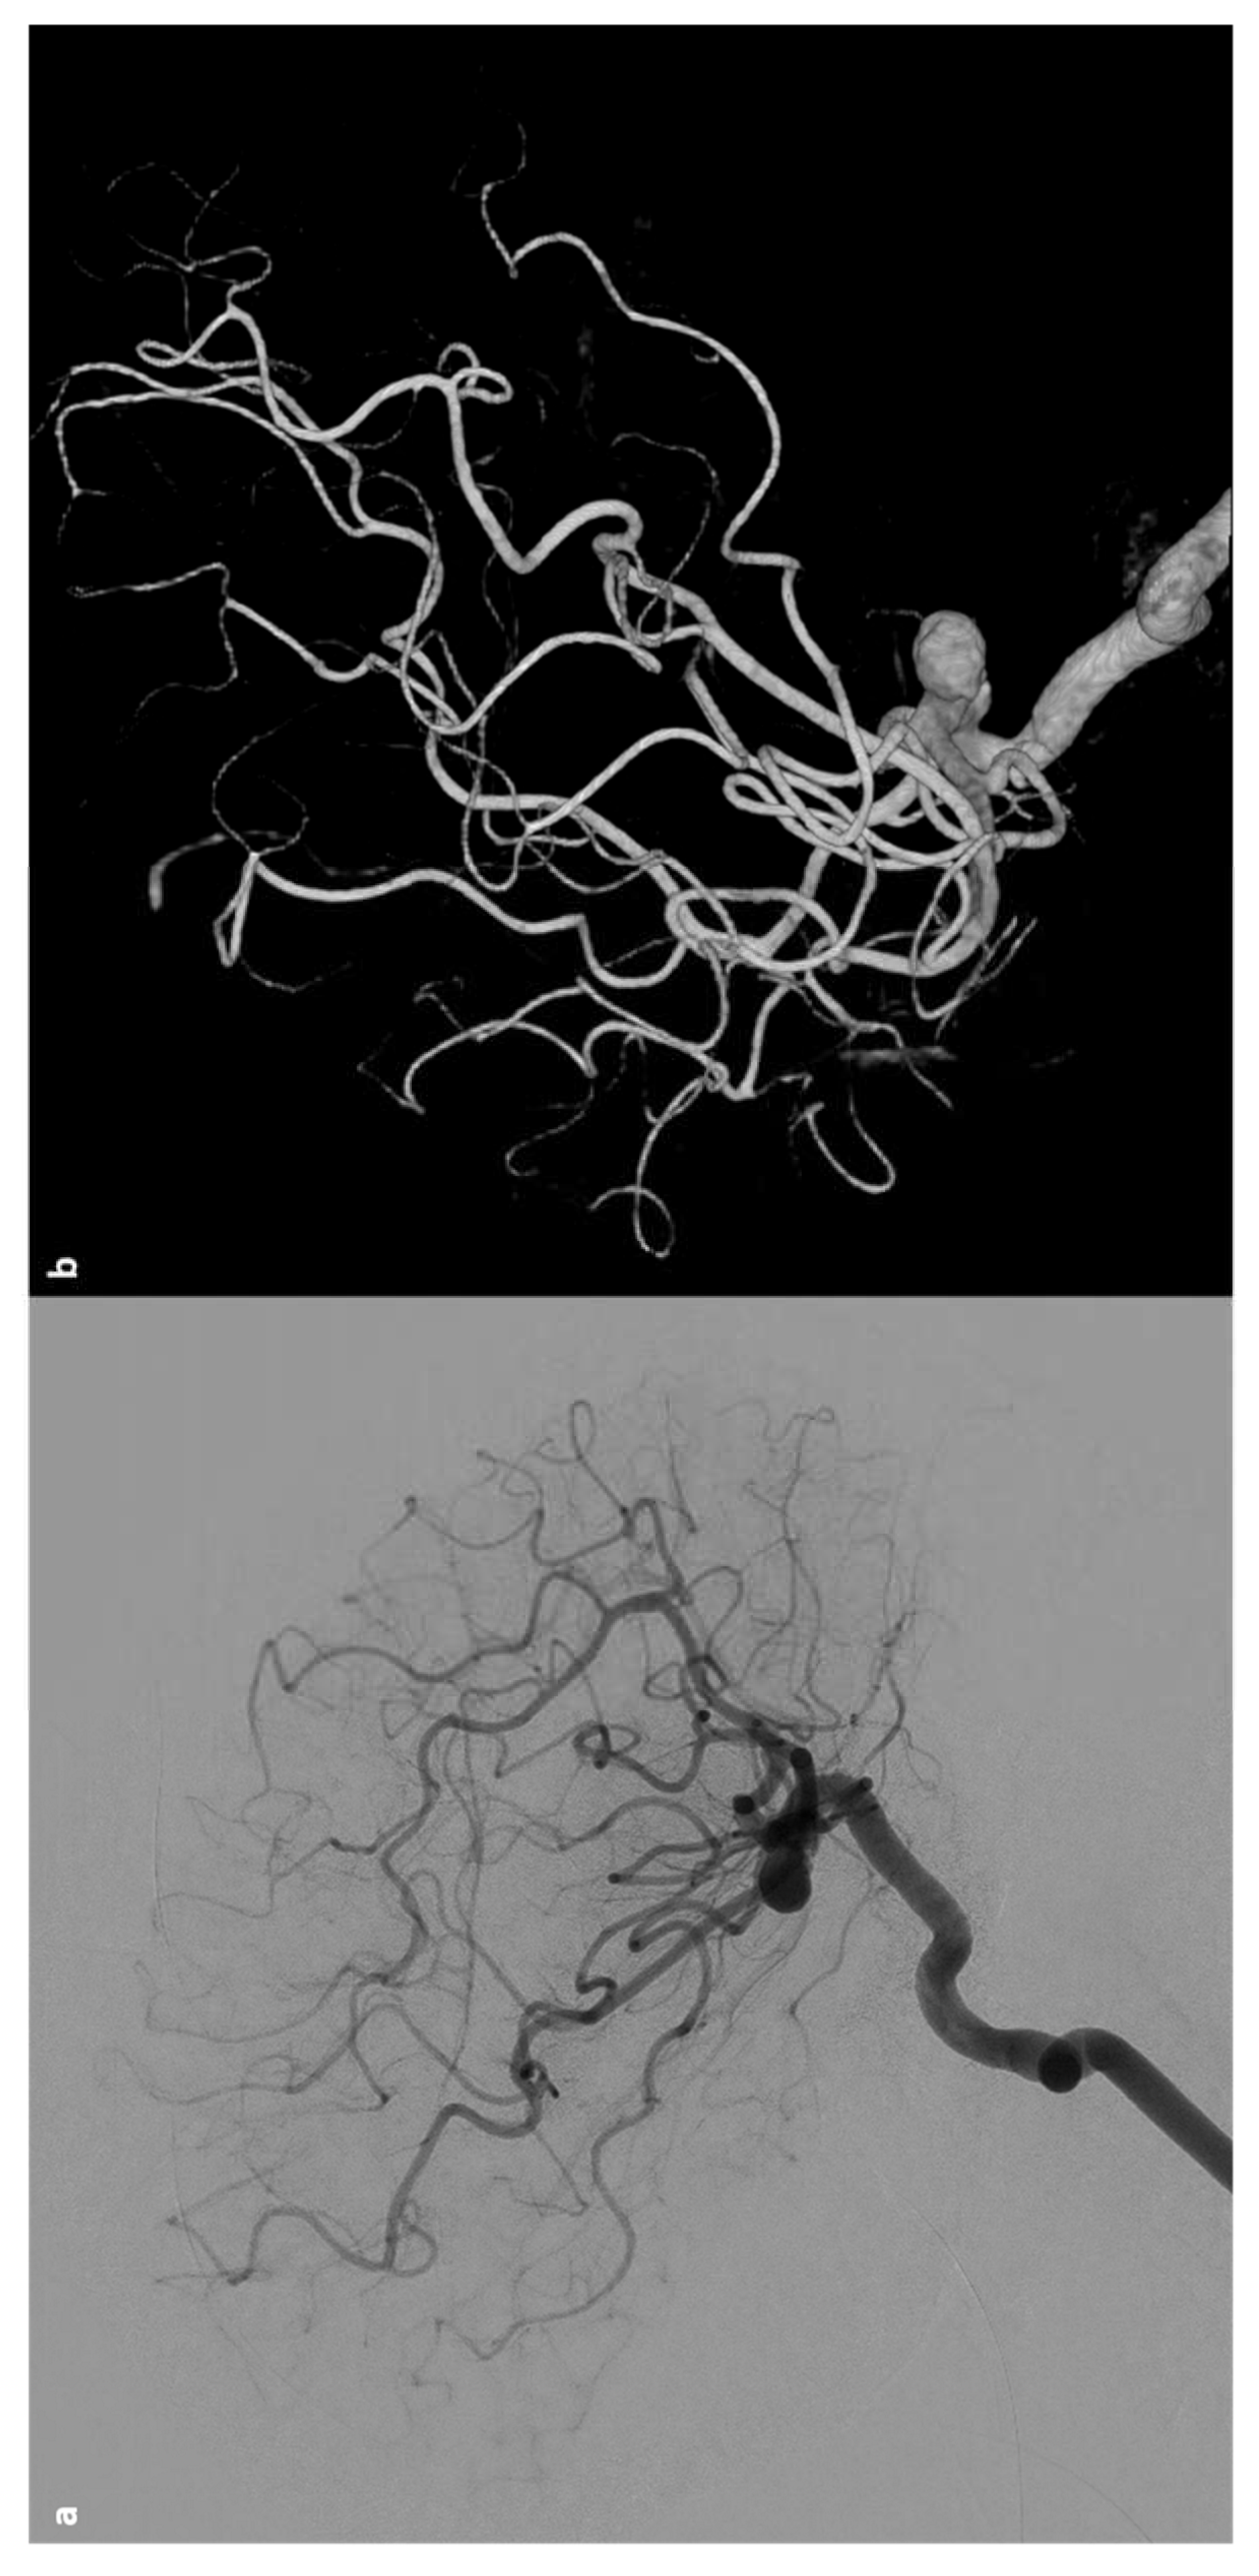

- Dobson SR, Holden KR, Nietert PJ, et al. Moyamoya syndrome in childhood sickle cell disease: a predictive factor for recurrent cerebrovascular events. Blood 2002;99:3144–50.

- Griessenauer CJ, Lebensburger JD, Chua MH, et al. Encephaloduroarteriosynangiosis and encephalomyoarteriosynangiosis for treatment of moyamoya syndrome in pediatric patients with sickle cell disease. J Neurosurg Pediatr 2015;16:64–73.

- Smith ER, McClain CD, Heeney M, et al. Pial synangiosis in patients with moyamoya syndrome and sickle cell anemia: perioperative management and surgical outcome. Neurosurg Focus 2009;26:E10.

- Fryer RH, Anderson RC, Chiriboga CA, et al. Sickle cell anemia with moyamoya disease: outcomes after EDAS procedure. Pediatr Neurol 2003;29:124–30.

- Seeler RA, Royal JE, Powe L, Goldberg HR. Moyamoya in children with sickle cell anemia and cerebrovascular occlusion. J Pediatr. (1978) 93:808–10. [CrossRef]

- Connes P, Verlhac S, Bernaudin F. Advances in understanding the pathogenesis of cerebrovascular vasculopathy in sickle cell anaemia. Br J Haematol. (2013) 161:484–98. [CrossRef]